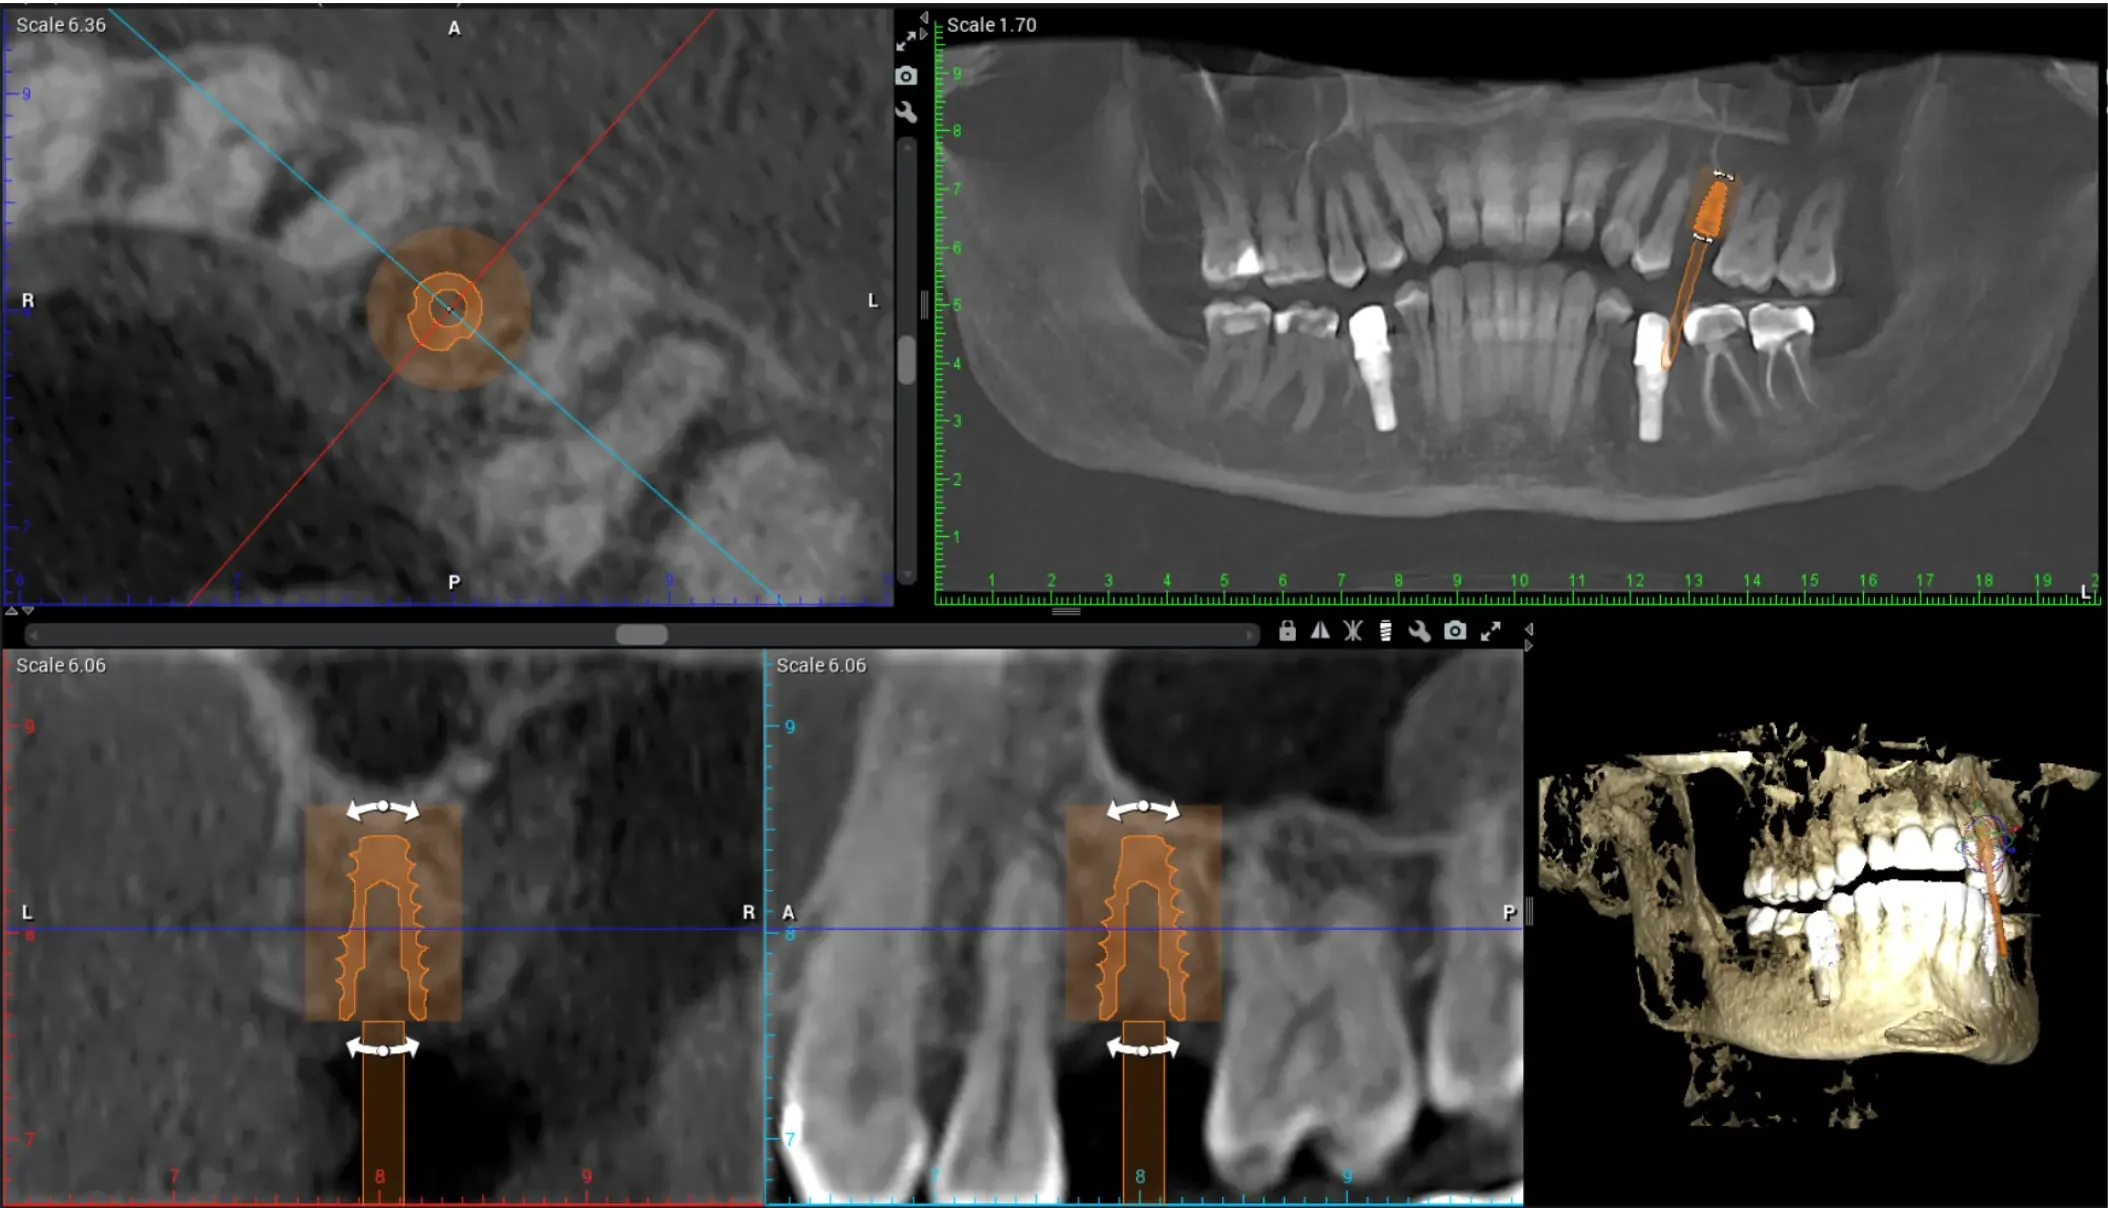

At Teuscher Legacy Dental, every implant case is planned with 3D cone beam CT imaging and digitally designed surgical guides — the same technology used by other leading surgical centers.

Visualize bone quality, and sinus anatomy, and nerve locations

Place implants with extreme precision

Often shorten healing time and improve comfort

Optimize location of future crown (the chewing part of the implant)

(Source: Vercruyssen et al., Clin Oral Implants Res 2014;25:94–99)

This first step also helps make sure the patient is on the same page with what to expect a final result to look like. We also go over financial details and timeline. This way the patient knows what to expect every step of the way!CBCT 3D Planning

Before taking any teeth out or diving into implant placement, we start with a CBCT scan to evaluate the bone structure in 3D. This shows us the height, width, and quality of bone, and how close we are to adjacent roots or anatomical structures. Planning the exact implant location here prevents complications later.Site Preparation & Grafting (if needed)

CBCT (3‑D imaging) is used to assess bone quantity and quality and check for any sinus or nerve issues. There should be an evaluation of overall health (e.g., diabetes, smoking, medications) and other risk factors. Gum health should also be assessed (are there active gum infections?) and whether bone grafting is needed.Use of guided surgical planning

CBCT imaging allows us to measure bone density, identify vital structures (like nerves and sinuses), and plan the exact position of your future implant.

Using digital treatment planning, we design a custom surgical guide to ensure the implant is placed with millimeter accuracy.